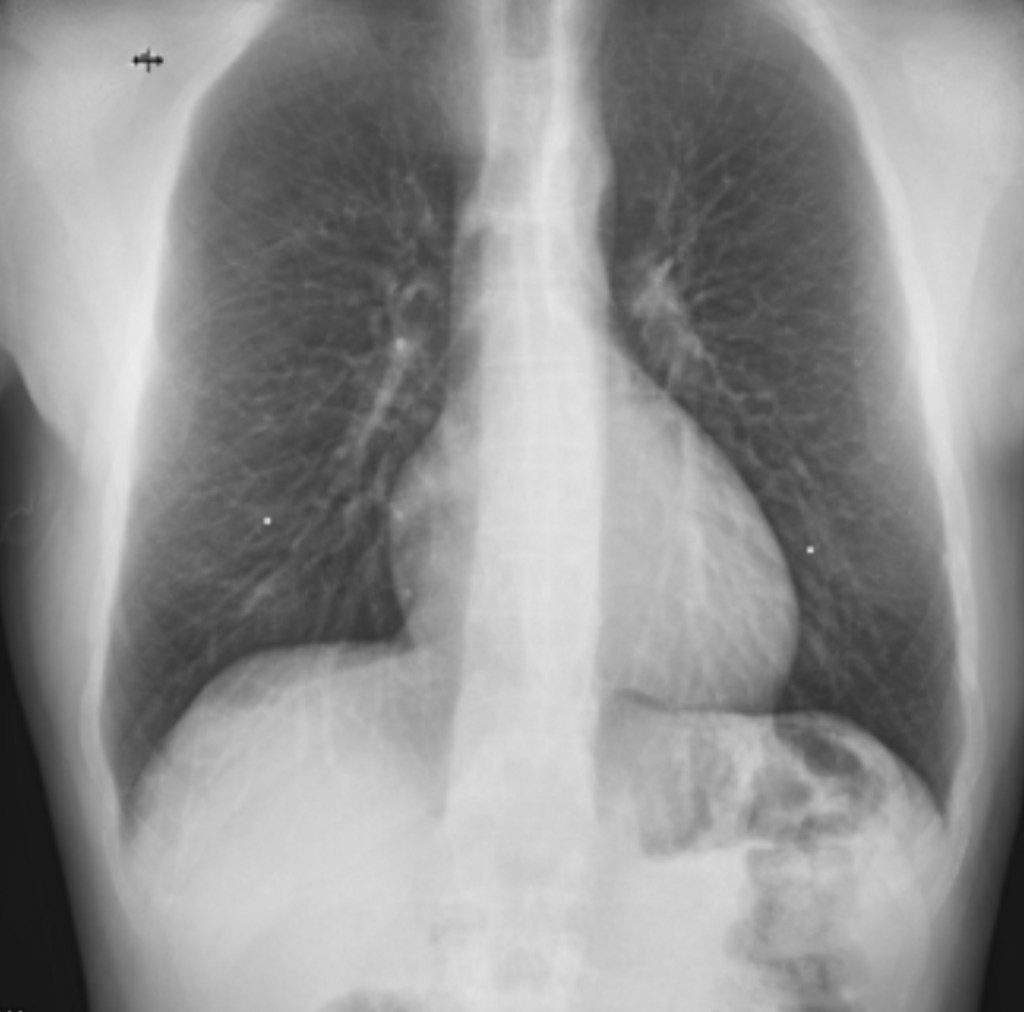

Imaging, overall, has been pretty minimal, which I’m definitely grateful for. So far, I’ve had two chest X-rays and a CT scan, all focused on my lungs.

The initial X-ray and CT scan were done around the same time earlier this year. While some pulmonologists might say the CT scan was a bit excessive, mine wanted to be sure we had a solid understanding of what shape my lungs were in before starting any kind of treatment or monitoring.

I agreed, because unfortunately, one of the other main areas the genetic mutation I have can affect is the lungs, so I wanted to make sure everything looked okay on that front. We also figured that it would be beneficial to have a baseline for comparison in case any issues come up down the line.

Both results (which I’ll share below) came back clear. I wasn’t expecting anything different, since I was still running without any issues, but it was still nice to get some good news at a time where it felt like good news was in short supply.

With my admission date approaching, we did one final chest X-ray a few weeks ago just to make sure everything still looked good, and it does. As you can imagine, being able to largely maintain my health throughout this whole process has meant a lot to me, and it’s always reassuring when the data backs that up.

As for the actual experience, the X-rays felt quick and straightforward, but the CT scan was definitely more daunting. Even if you’re not claustrophobic, some discomfort is to be expected. The doughnut type machine they use is loud and definitely a little nerve-wracking, but I kept reminding myself they wouldn’t be putting me through it unless the information they were gathering was important.